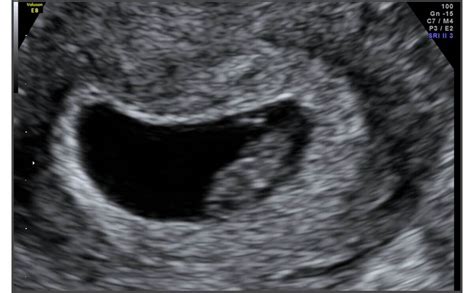

شكل الجنين الذكر في الشهر الثاني بالسونار

يمكن للطبيب معرفة جنس المولود بالسونار إذا كان الجنين ذكرًا من خلال ضربات القلب، فيكون معدل ضربات قلب الجنين الذكر أكثر من 140 نبضة في الدقيقة، لكن هذه الطريقة ليست دقيقة بنسبة 100٪